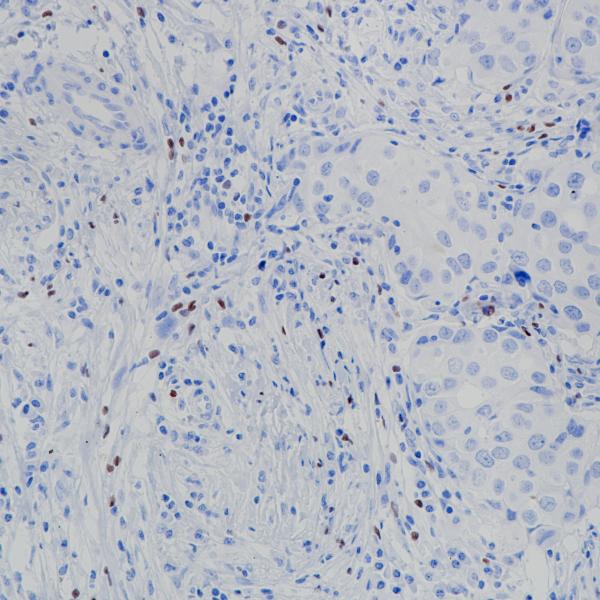

BP6166